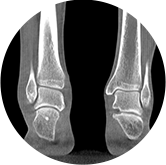

足踝

VR體繪制重建